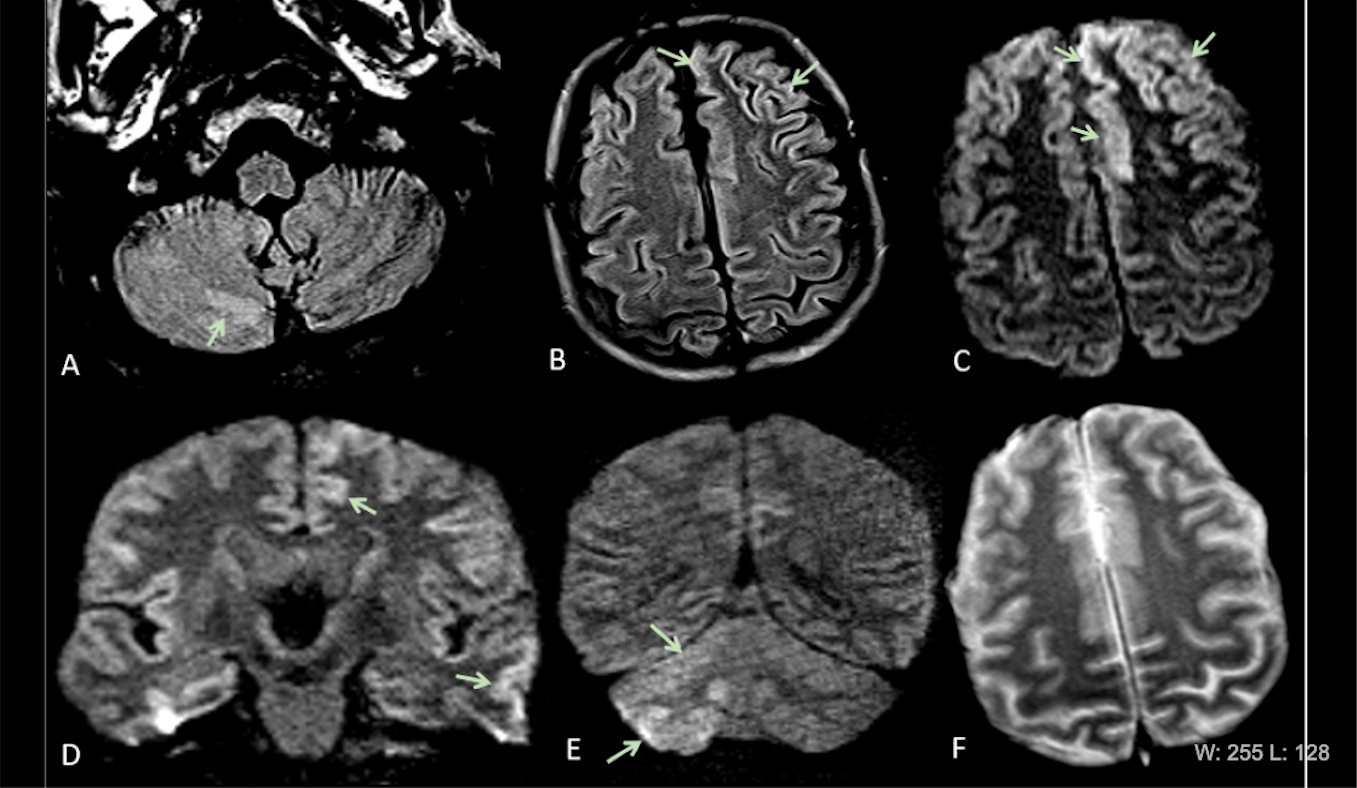

This photo gallery shows the variety of radiological presentations of COVID-19 (SARS-CoV-2) in medical imaging, including computed tomography (CT), radiograph X-rays, ultrasound, echocardiograms and magnetic resonance imaging (MRI). The radiology images show examples of typical COVID pneumonia in the lungs and the numerous complications the virus causes in the body in multiple organs, including the brain, kidneys, heart, abdomen and vascular system.